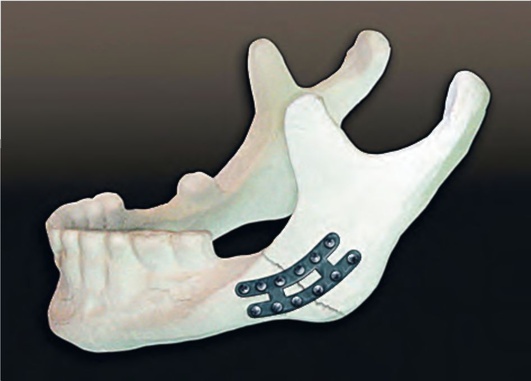

Остеосинтез скуловой

Остеосинтез скуловой 90 фото